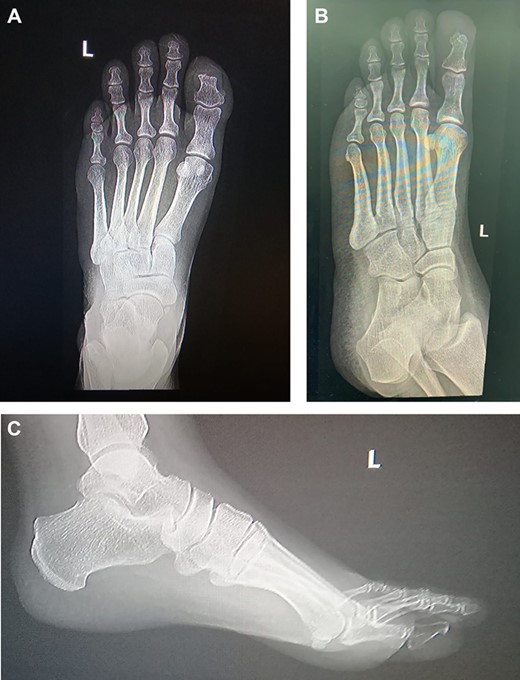

The laboratory data included a white blood cell count of 6000/μl, hemoglobin of 10.5 g/dl, platelet count of 233 × 10/μl, blood glucose 121 mg/dl, blood urine nitrogen 46 mg/dl, serum creatinine 69 mg/dl, sodium 138 mmol/L, potassium 3.8 mmol/L, serum albumin 3.4 g/dl, erythrocyte sedimentation rate 73 mm/h, and C-reactive protein 15.6 mg/dl. The X-ray of lower extremity revealed no significant abnormality (Fig. 1).

Left foot X-ray 19 months post excision and coverage with Kutler bilateral V-Y advancement flaps no evidence of recurrence.